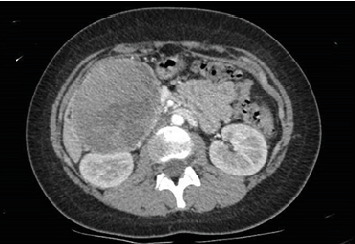

Abstract Image

Solid pseudopapillary neoplasms (SPNs) represent a tumor of the exocrine pancreas, belonging to the group of pancreatic cystic neoplasms. It is exceedingly uncommon for SPNs to manifest in extrapancreatic locations, such as the mesocolon, greater omentum, jejunum, and ovary. SPNs are considered very rare, constituting about 0.17%-2.5% of all pancreatic neoplasms and 6% of cystic pancreatic neoplasms. We present two pediatric cases of SPNs: one involving a 16-year-old female patient and the other a 14-year-old girl, both diagnosed and treated in our center with surgical resection. The experience of our center confirms that wide margin surgery, with associated metastasectomy if necessary, represents the therapy of choice for SPNs, ensuring effective control of the disease.